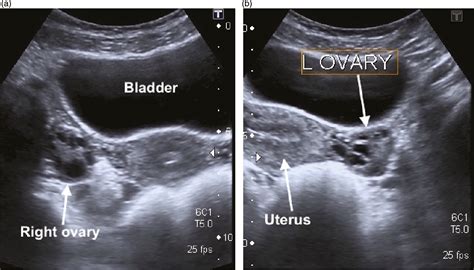

• Transabdominal Ultrasound: The technician applies gel to your abdomen and moves a transducer over the skin. This typically requires a full bladder to provide a better acoustic window.

• Transvaginal Ultrasound: A specialized, slim transducer is inserted into the vagina. This method provides much clearer, more detailed images of the ovaries and uterus because the probe is closer to these organs.

When a radiologist or sonographer reviews a normal ovary ultrasound, they are looking for specific anatomical markers. It is important to remember that ovaries change throughout the menstrual cycle and across a person's lifespan, so "normal" can look different depending on your age and hormonal status.

• Position: The ovaries should be located in their expected anatomical position within the pelvis, typically lateral to the uterus.

When you receive the results of your normal ovary ultrasound, you might see medical terminology that seems confusing. Phrases like "normal echotexture" or "no adnexal masses seen" are excellent indicators. "Adnexa" refers to the area near the uterus, which includes the ovaries and fallopian tubes. Therefore, seeing "no adnexal masses" simply means the technician did not find any abnormal lumps, growths, or suspicious cysts in that area.